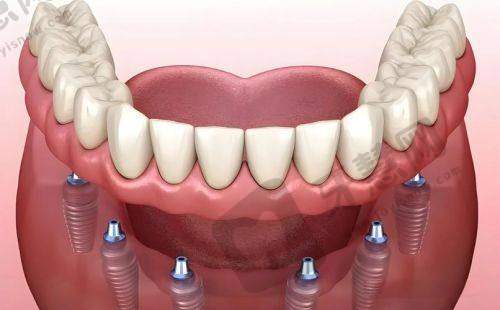

前牙美学种植的重要性:前牙美学种植不仅要修复牙齿的咀嚼功能,更要注重牙齿的美观度,让患者在进食和微笑时都能展现自然、美观的牙齿状态。南宁岭南口腔凭借精良技术和丰富经验,在该项目上独具优势。

技术优势:2009 年掌握上颌窦开窗植骨种牙术和下齿槽神经避让种牙术,实现即拔即种,为前牙美学种植提供坚实技术支持,减少手术创伤和风险。